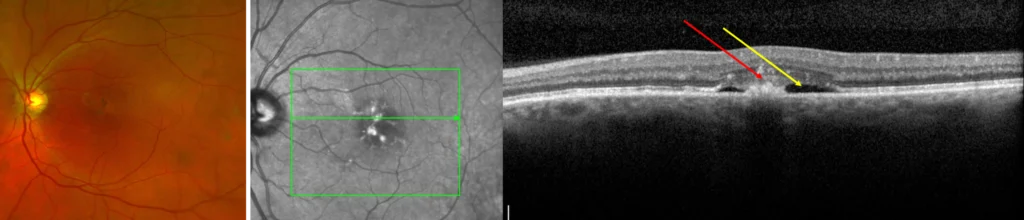

A doctor may use multiple methods in order to diagnose AMD, such as a dilated retinal examination or an optical coherence tomography (OCT) scan. An OCT scan is a painless photograph that provides a cross-sectional scan through the macula so that microscopic details of the macula can be discerned.

In some patients, a fluorescein angiography may be used. In this procedure, a dye is injected into the arm, from which to travels through the blood to the eye. Photographs are taken of the eye which map out all the blood vessels and blood flow in the retina. This test identifies areas of blood flow loss as well as areas of new blood vessel grown (neovascularization).